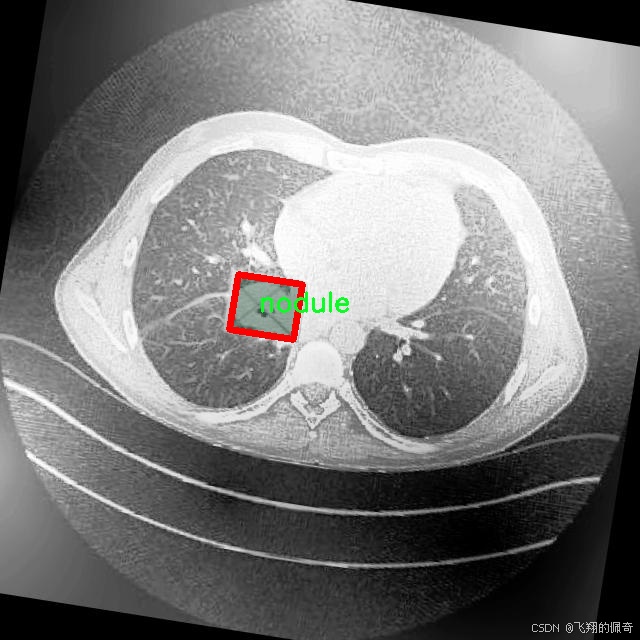

肺结节的早期检测与诊断对于降低肺癌的死亡率至关重要。根据世界卫生组织的统计数据,肺癌已成为全球范围内导致癌症相关死亡的主要原因之一。肺结节的出现往往是肺癌的早期信号,因此,准确、快速地识别和分割肺结节图像对于临床决策和患者预后具有重要意义。传统的肺结节检测方法依赖于放射科医生的经验和判断,然而,随着医学影像数据量的急剧增加,人工分析的效率和准确性面临着严峻挑战。因此,基于深度学习的自动化图像分割技术逐渐成为研究的热点。

在众多深度学习模型中,YOLO(You Only Look Once)系列因其高效的实时目标检测能力而受到广泛关注。YOLOv8作为该系列的最新版本,具备了更强的特征提取能力和更快的处理速度,适合用于医学图像分析。尽管YOLOv8在目标检测领域表现出色,但在肺结节图像分割任务中仍存在一定的局限性,尤其是在处理小尺寸结节和复杂背景时。因此,改进YOLOv8以增强其在肺结节图像分割中的表现,具有重要的学术价值和实际意义。

本研究将基于改进的YOLOv8模型,构建一个高效的肺结节图像分割系统。所使用的数据集包含1600幅图像,涵盖了三类重要的病理类型:腺癌、癌症和结节。这些数据不仅为模型的训练提供了丰富的样本,也为后续的模型评估和验证奠定了基础。通过对不同类别的肺结节进行精确分割,研究旨在提高模型在实际应用中的鲁棒性和准确性,进而为临床医生提供更为可靠的辅助诊断工具。